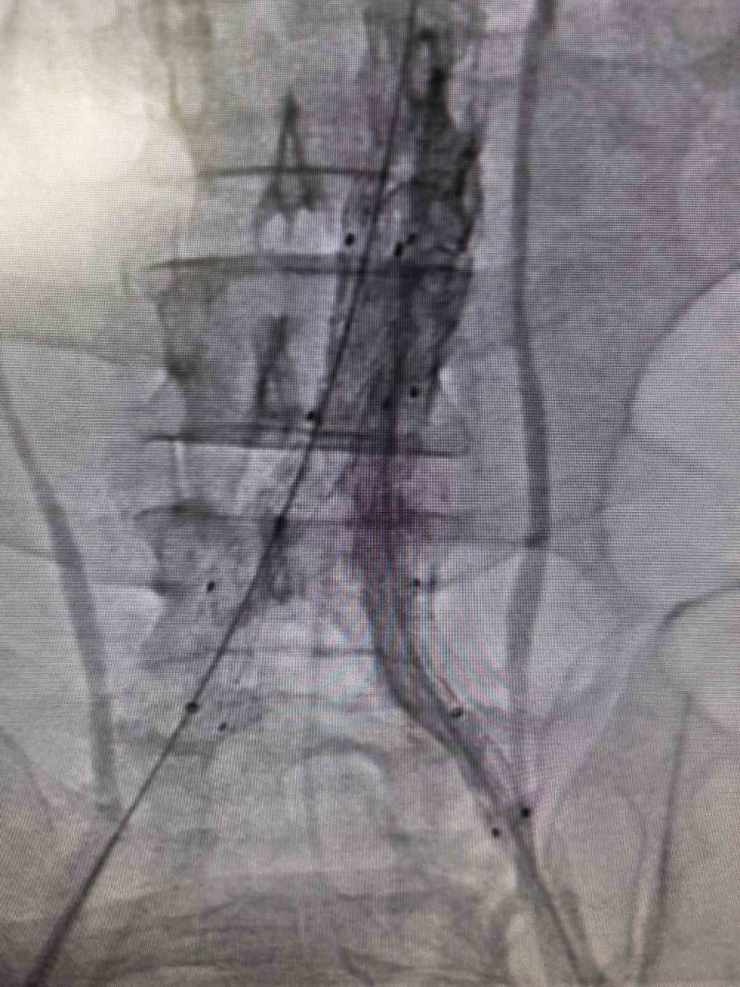

Bilecik Eğitim ve Araştırma Hastanesi'nde daha önce farklı sağlık kuruluşlarına başvuran ancak net bir tanı konulamayan hasta, acil servisinde yapılan detaylı tetkikler sayesinde doğru tanıya ulaştırıldı. Şiddetli sırt ve karın ağrısı şikâyetiyle hastaneye başvuran 39 yaşındaki Mehmet D.'nin acil serviste çekilen ileri görüntüleme tetkiklerinde, kalpten çıkan ana damarın iç duvarında yırtılma olduğu belirlendi. Hayati risk taşıyan bu durum üzerine hasta, kalp ve damar cerrahisi ekibi tarafından acil olarak değerlendirmeye alındı.Hasta, Kalp ve Damar Cerrahisi Uzmanı Op. Dr. Elmas Üreyen tarafından kapalı yöntemle tedavi edildi. Damar içinden girilerek yapılan işlem sırasında, yırtılan ana damarın içine özel bir stent yerleştirildi ve damar içten onarıldı. Açık ameliyata gerek kalmadan gerçekleştirilen bu yöntem sayesinde hasta kısa sürede rahatladı.Tedavi sonrası yakından takip edilen hastanın ağrılarının tamamen geçtiği, genel sağlık durumunun iyi olduğu gözlemlendi. Kontrollerinin sorunsuz seyretmesi üzerine hasta sağlıklı bir şekilde taburcu edildi.

Konuyla ilgili açıklama yapan Op. Dr. Elmas Üreyen, "Bu tür damar yırtılmaları ani gelişebilen ve zamanında müdahale edilmezse hayati risk taşıyan durumlardır. Hastamızda erken tanı koyarak kapalı yöntemle müdahale ettik. Açık ameliyata gerek kalmadan yapılan bu işlem, hastanın hem daha hızlı iyileşmesini hem de günlük yaşamına kısa sürede dönmesini sağladı. Hastanemizde, ileri teknoloji tıbbi cihazlar ve deneyimli hekim kadrosu ile bu tür yüksek riskli damar hastalıklarının tanı ve tedavisi başarıyla gerçekleştirilmektedir. Kapalı yöntemlerle uygulanan bu tedaviler, hastalara daha konforlu bir süreç sunarken, iyileşme süresini de önemli ölçüde kısaltmaktadır" dedi.